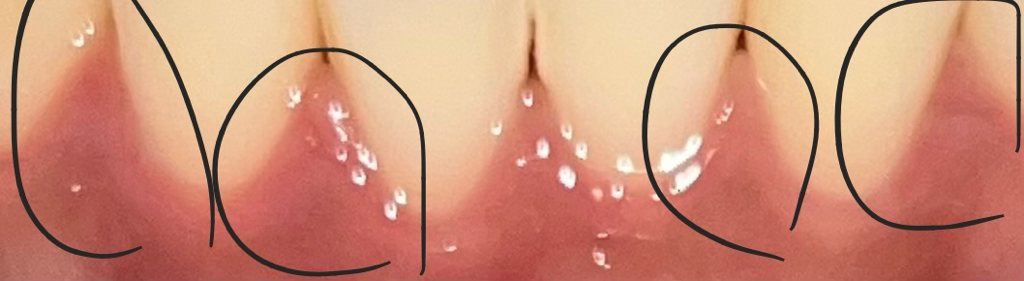

치간유두 부은거같이 빨개요 ㅜㅜ

약간 부푼거같이 평평하지않고 빨갛게 부은거같아요 염증일까요 ?̊̈ 치실이나 양치를쎄게해서 부은걸까요 ?̊̈ 사진에서는 잘안보이는데 잇몸이좀 달라요,,,, ㅜㅜ

사진상으론 잘 보이지 않지만 해당 부위 통증이 있다면 염증에 의한 증상일 가능성이 높으며 치과 가보시는 게 좋습니다.

치실이나 치간칫솔을 너무 강하게 햇다면 마찰력때문에 잇몸이 저렇게 될수 잇습니다. 일시적인 현상이니 너무 걱정은 안하셔도 될것같습니다.

사진으로 봤을 때는 크게 이상이 없어 보입니다. 잇몸에 너무 자극을 주게 되면 붉게 변하는 경우도 있으니 잇몸에 가해지는 자극을 줄여주는 것이 좋습니다.